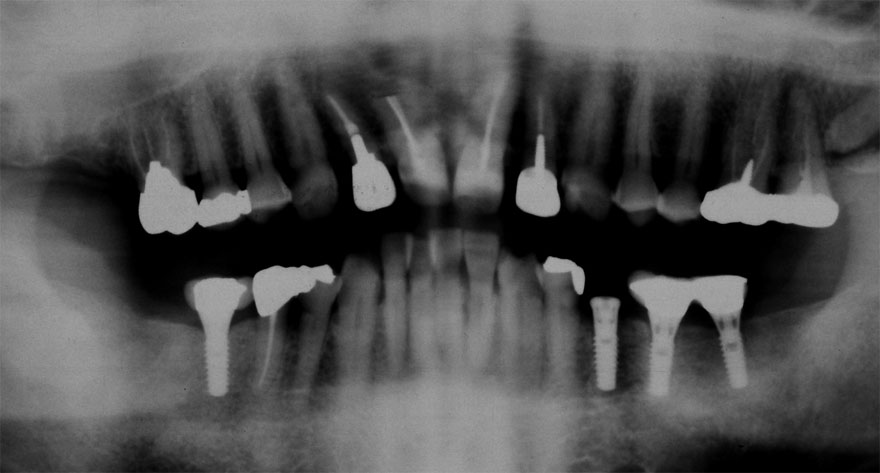

開始年齢 30代

初診時 30歳 女性 平均歯槽骨喪失量:1.46mm

22年後 52歳

平均歯槽骨喪失量:1.55mm

22年間喪失量:-0.09mm

年間喪失速度:-0.004mm

(ケア頻度:1.76ヵ月ごと)